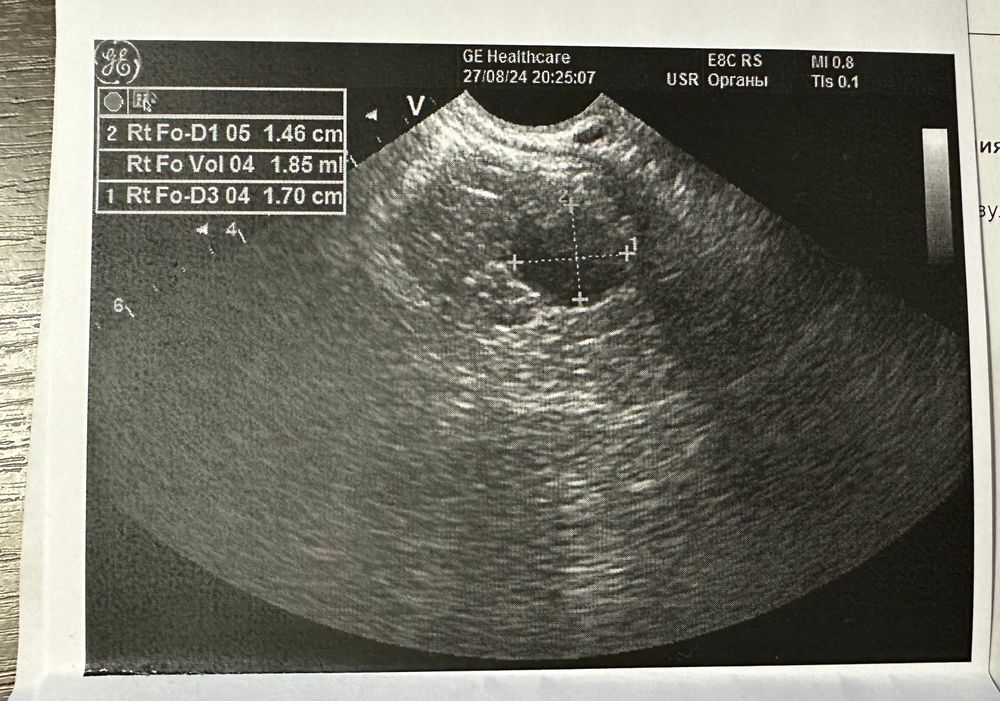

Была на узи на 22 дц, ДФ был 14 мм, эндометрий 1 см, на 25 дц тест на овуляций прям горел, потом через 3 дня начались прогестероновые выделения. Сегодня на 31 дц сходила на фолликулометрию, уже 5 дпо, жидкости нет, сказали, что теоретические ее уже может и не быть на 5 дпо, эндометрий 1 см, и под самый конец узи врач нашла типа дф 17 мм. Не понимаю как такие выделения если не было овуляции и как дф вырос только на 3 мм за 10 дней. Васкуляризацию не смотрела, и теперь сижу и гадаю могла ли она перепутать дф с жт? Поделитесь своими историями🙏❤️

Екатерина , грош цена такому узисту. Эндометрий описывают, при осмотре доминанта включают цдк, кровоток смотрят. Их путают с кистозным жт. Мое жт